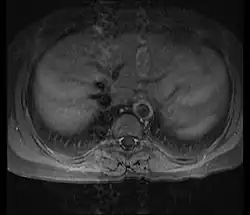

Non-invasive imaging is critical for diagnosing and monitoring. Magnetic resonance angiography (MRA) and computed tomography angiography (CTA) are often sufficient to visualize vessel narrowing, occlusion, or aneurysm formation.[18] MRA uses radio waves and magnetic fields to produce detailed cross-sectional images of blood vessels, often enhanced with contrast agents.[19] CTA, in turn, combines X-ray imaging and computer analysis with contrast due to assess both vessel structure and blood flow.[19]